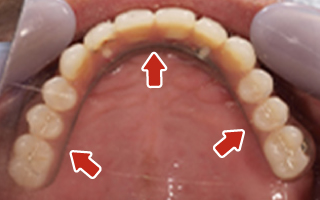

Before

After

| 68歳 男性 | 紹介 |

|---|---|

| 主訴 | れ歯が合わない 食べにくい 人生を豊かにしたい |

| 処置内容 |

上顎4本で12歯(オールオン4)、下顎4本5歯 上下抜歯即時埋入、即時荷重(手術当日にインプラントの上に仮歯装着) |

| 治療費用 | 上顎: 約220万(税込) 下顎: 約180万円(税込) |

| 治療期間 | 上顎: 9ヶ月 下顎: 6ヶ月 |

| リスク |

術後の腫れ、痛み(ピークは3日後、1週間で軽減) 上部構造物、仮歯の破折、人工歯根脱落リスクがあります |